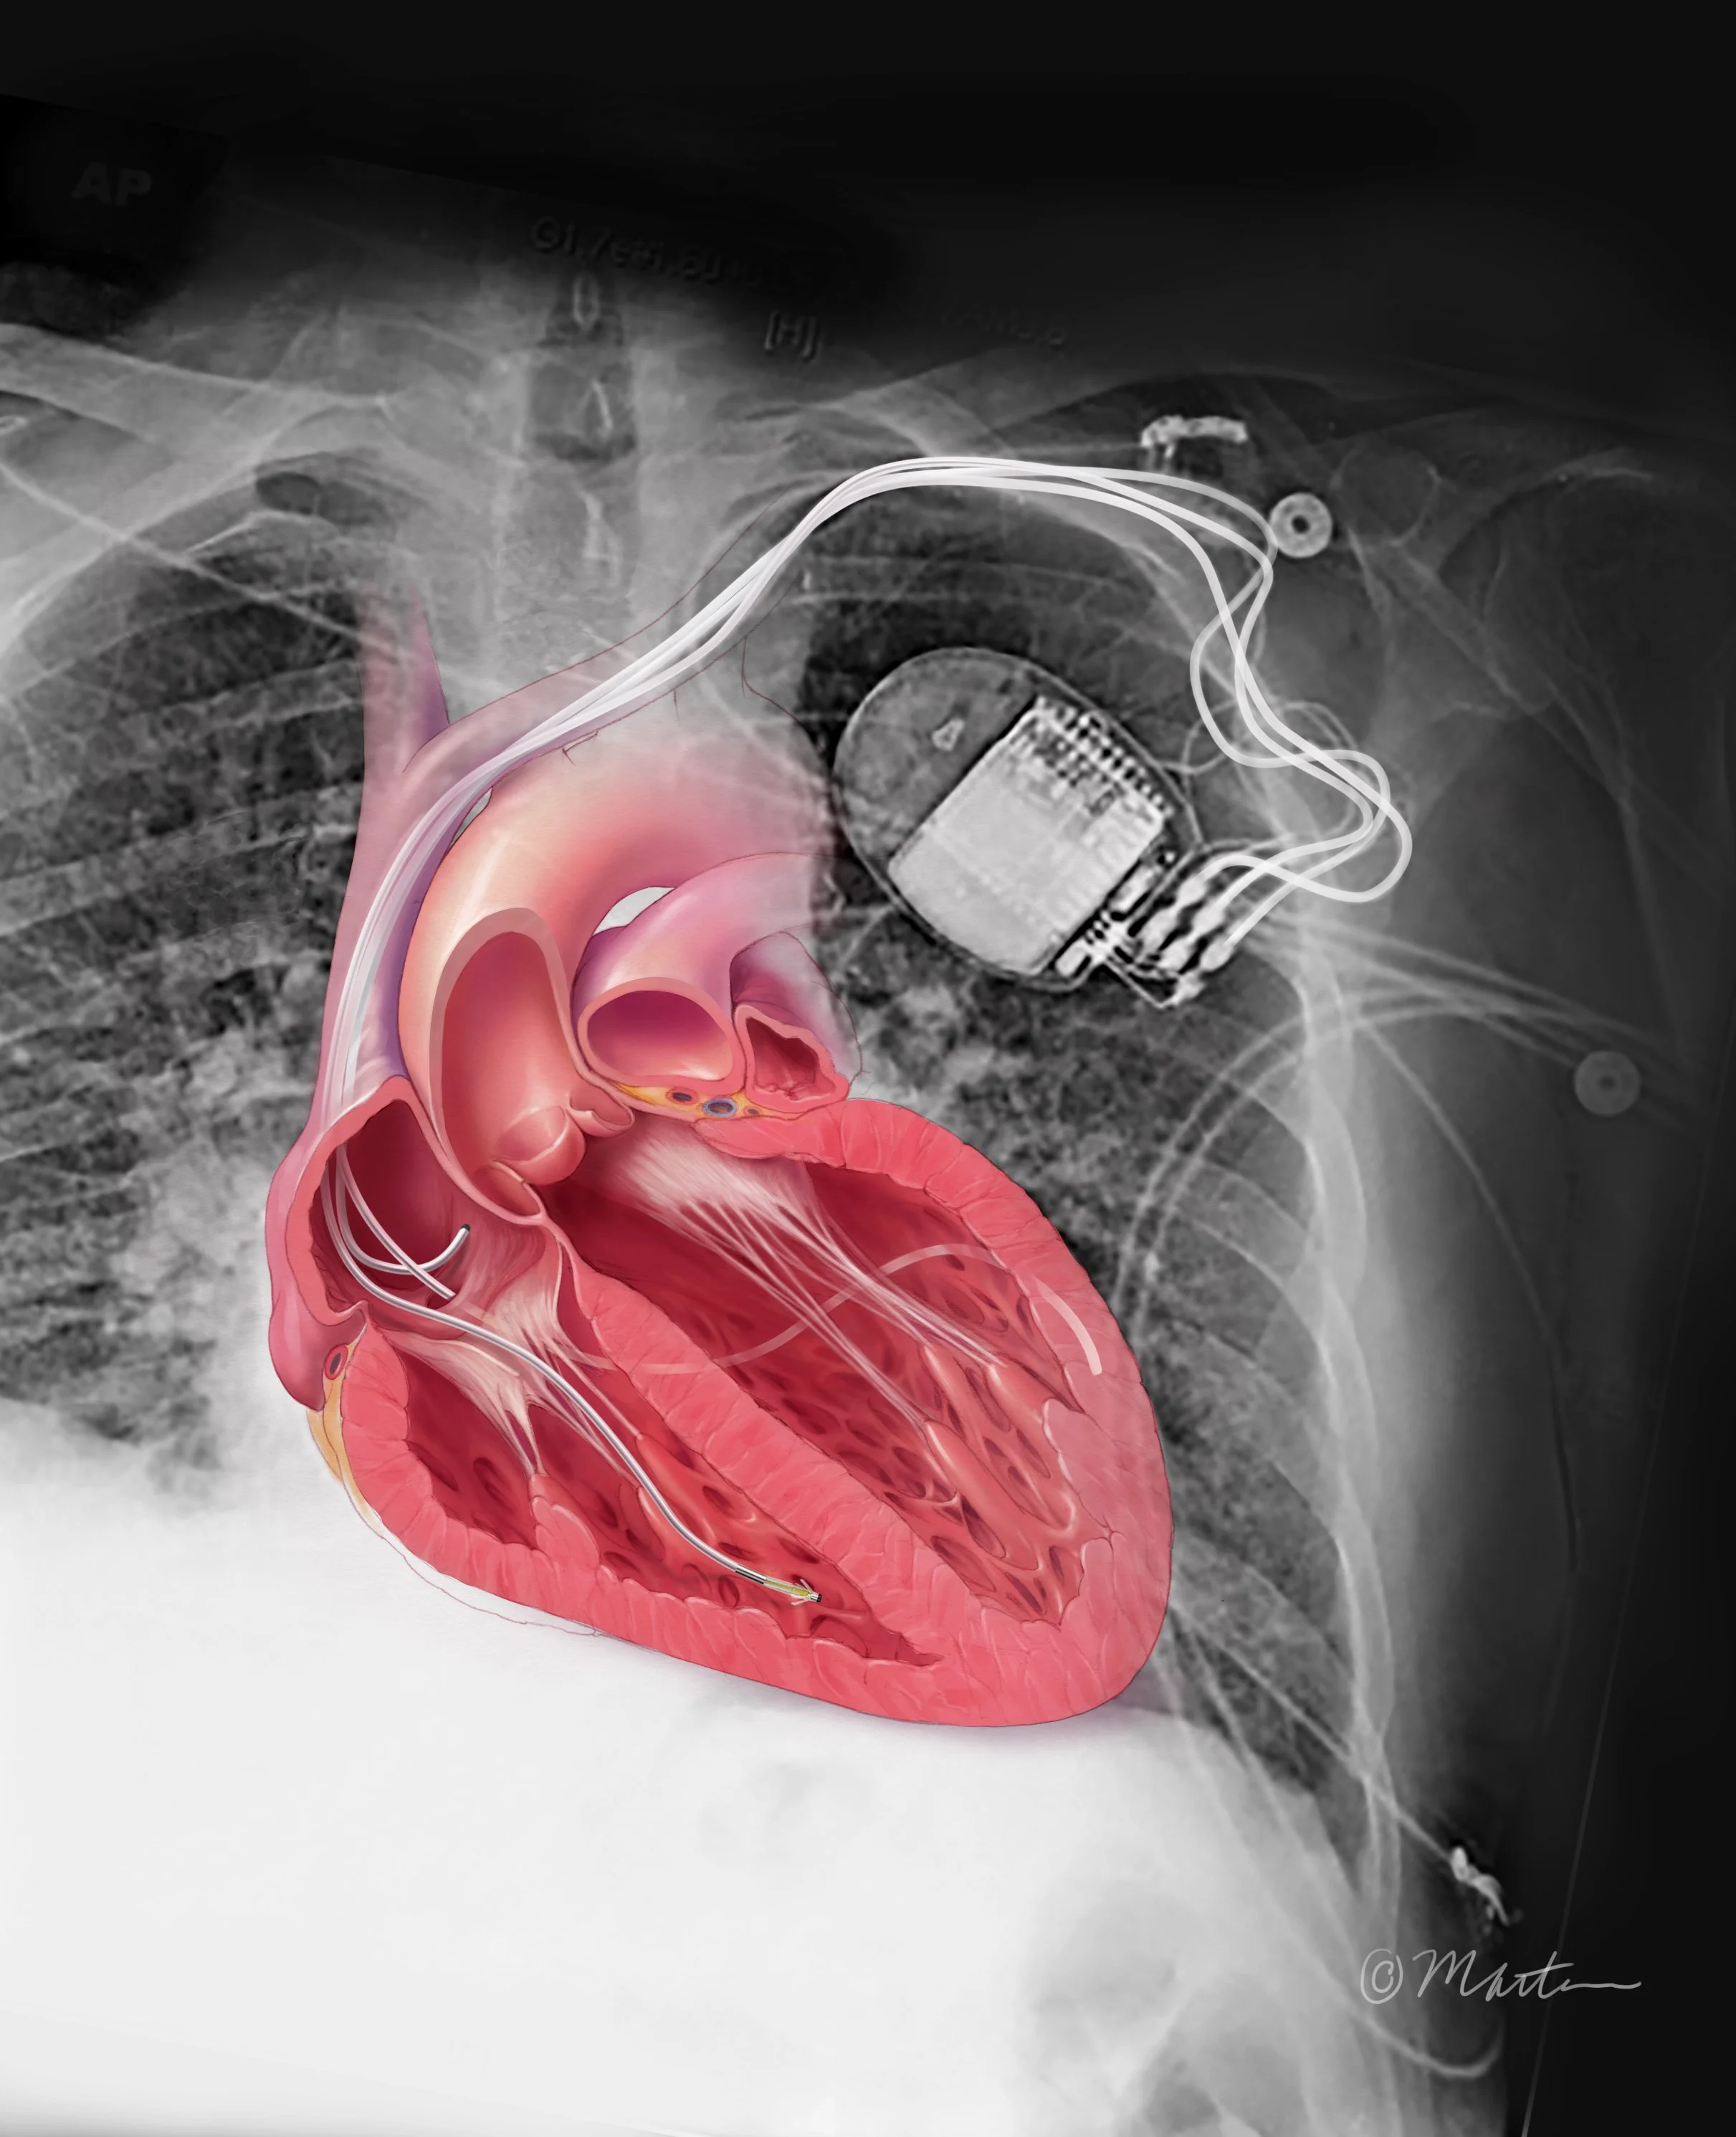

Biventricular Pacemaker